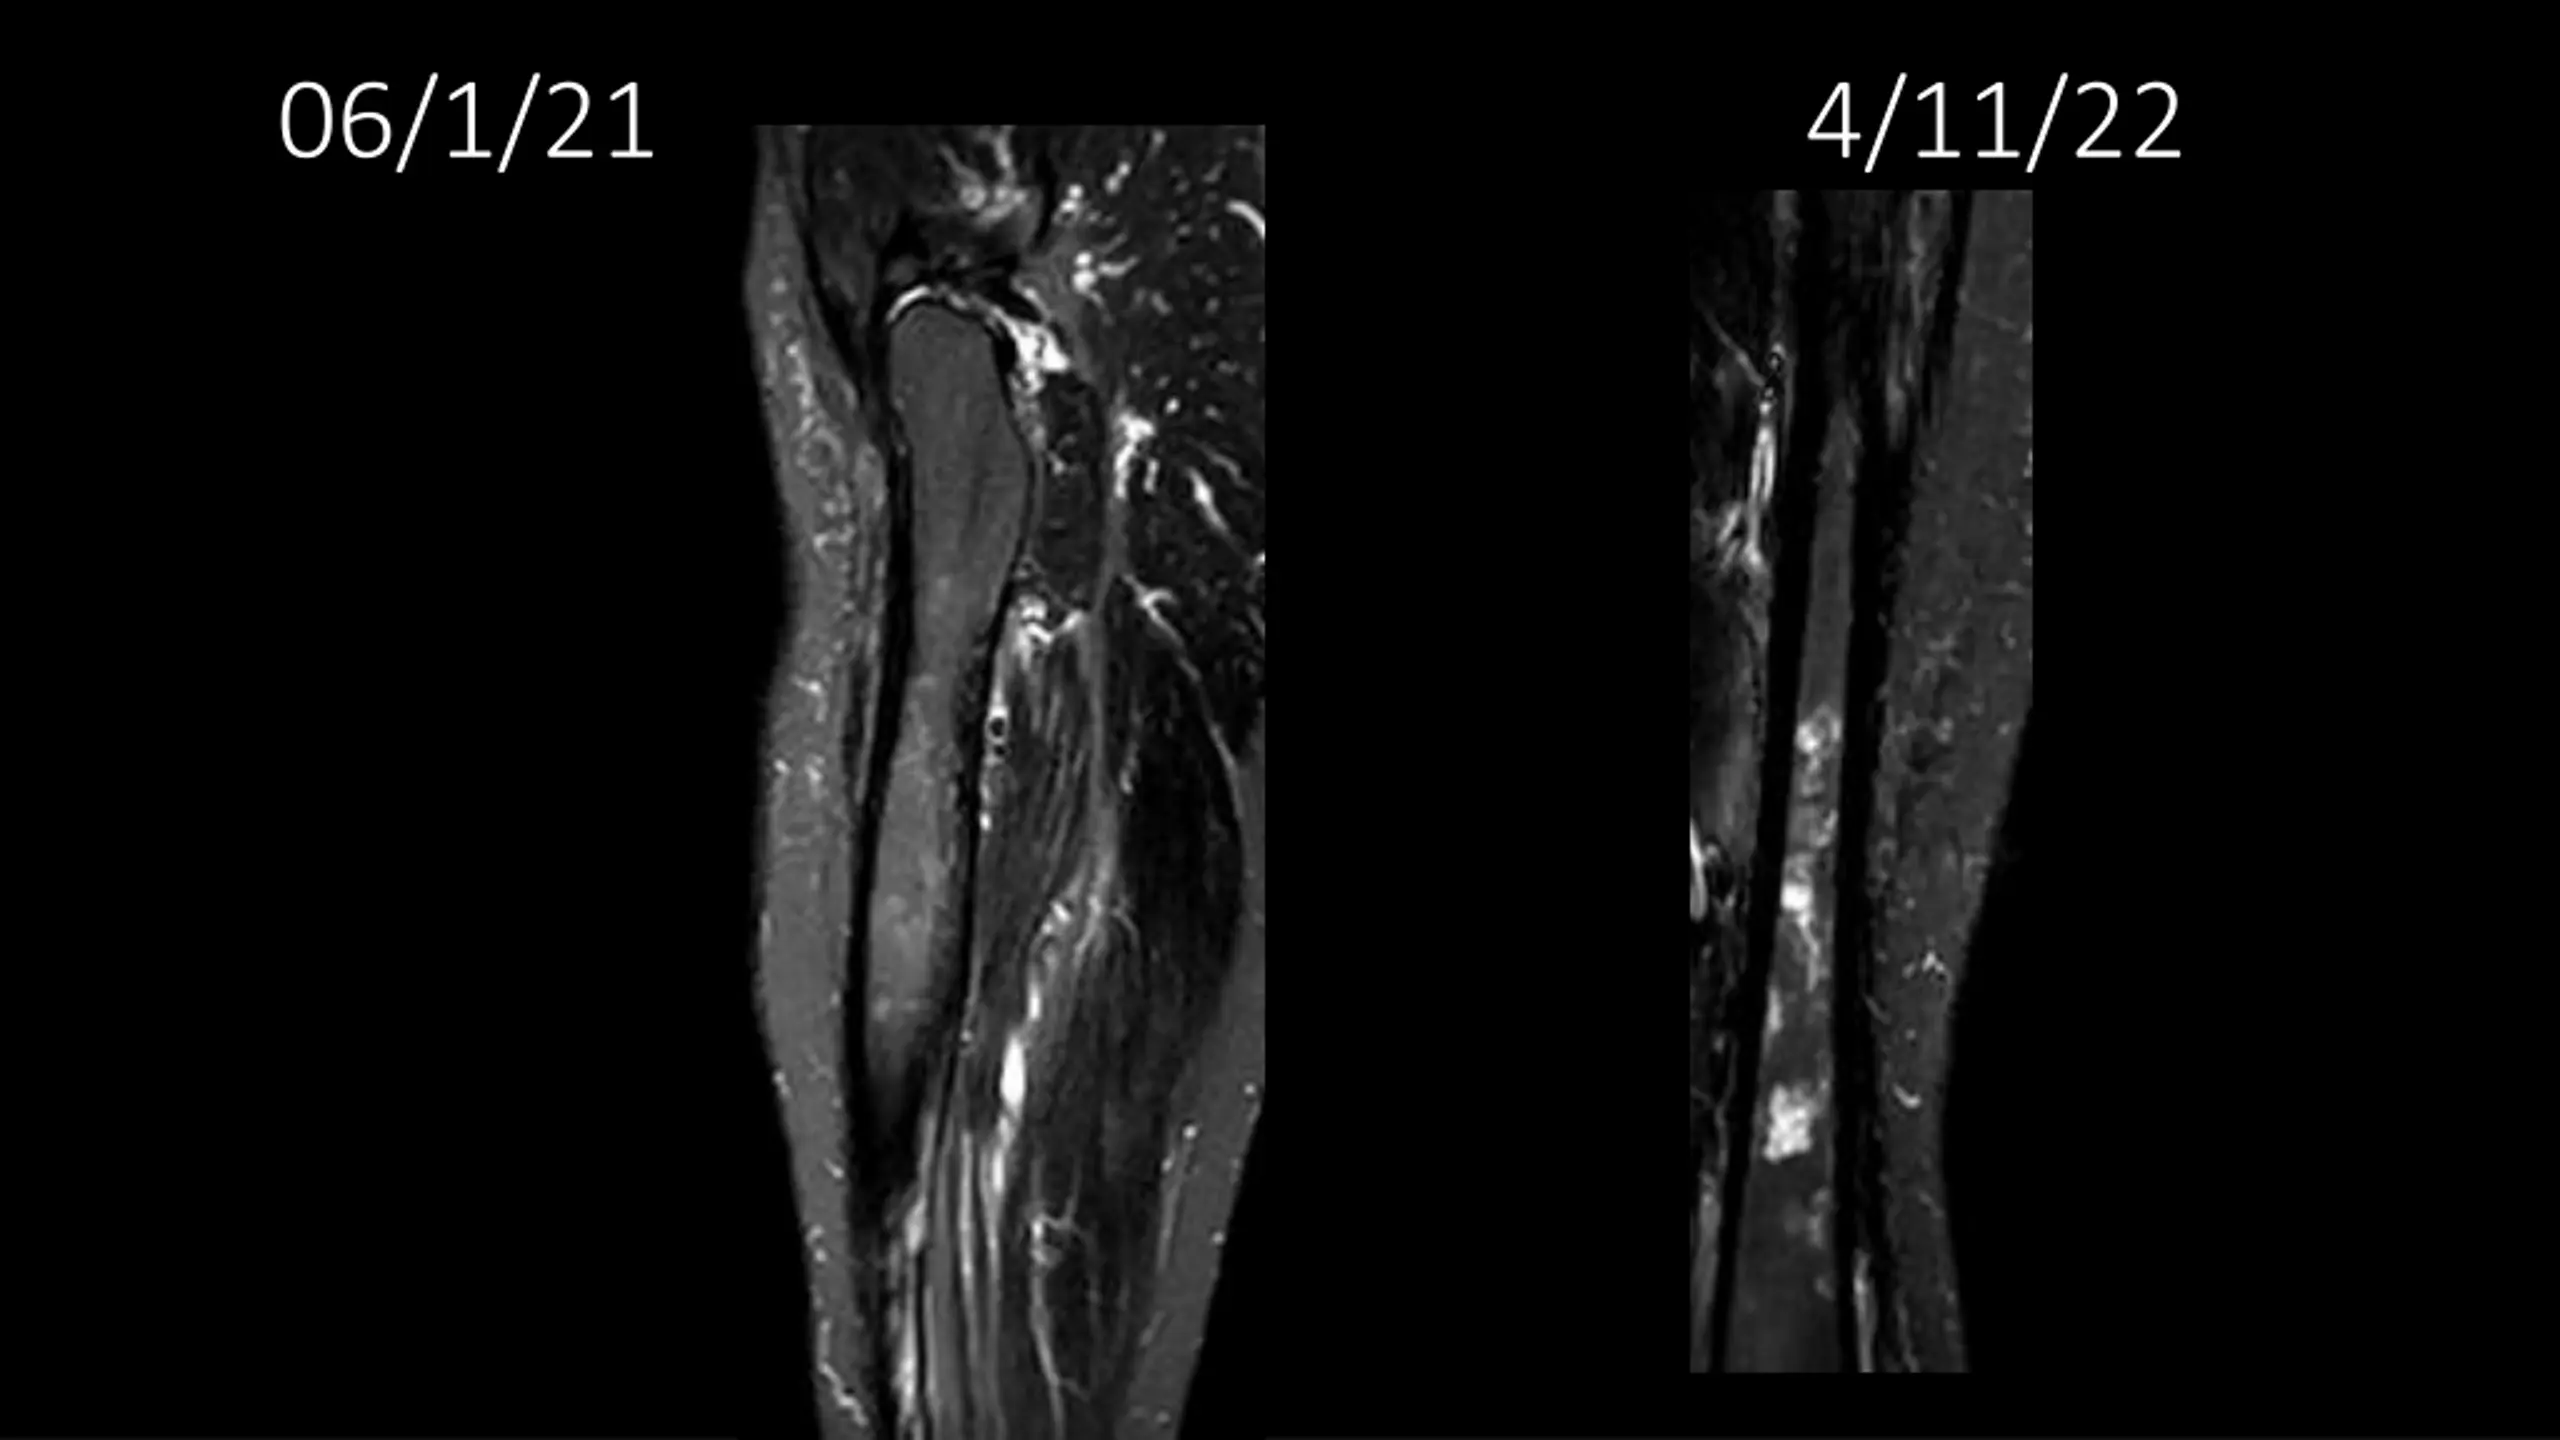

62-year-old shows post-surgery progress from 11/4/2020 to 4/11/22

Explore the journey of a 62-year-old individual post-UPS resection on 11/4/2020, through a series of dated images leading up to 4/11/22. Witness the transformation and recovery process in these visual updates reflecting the progression over time.